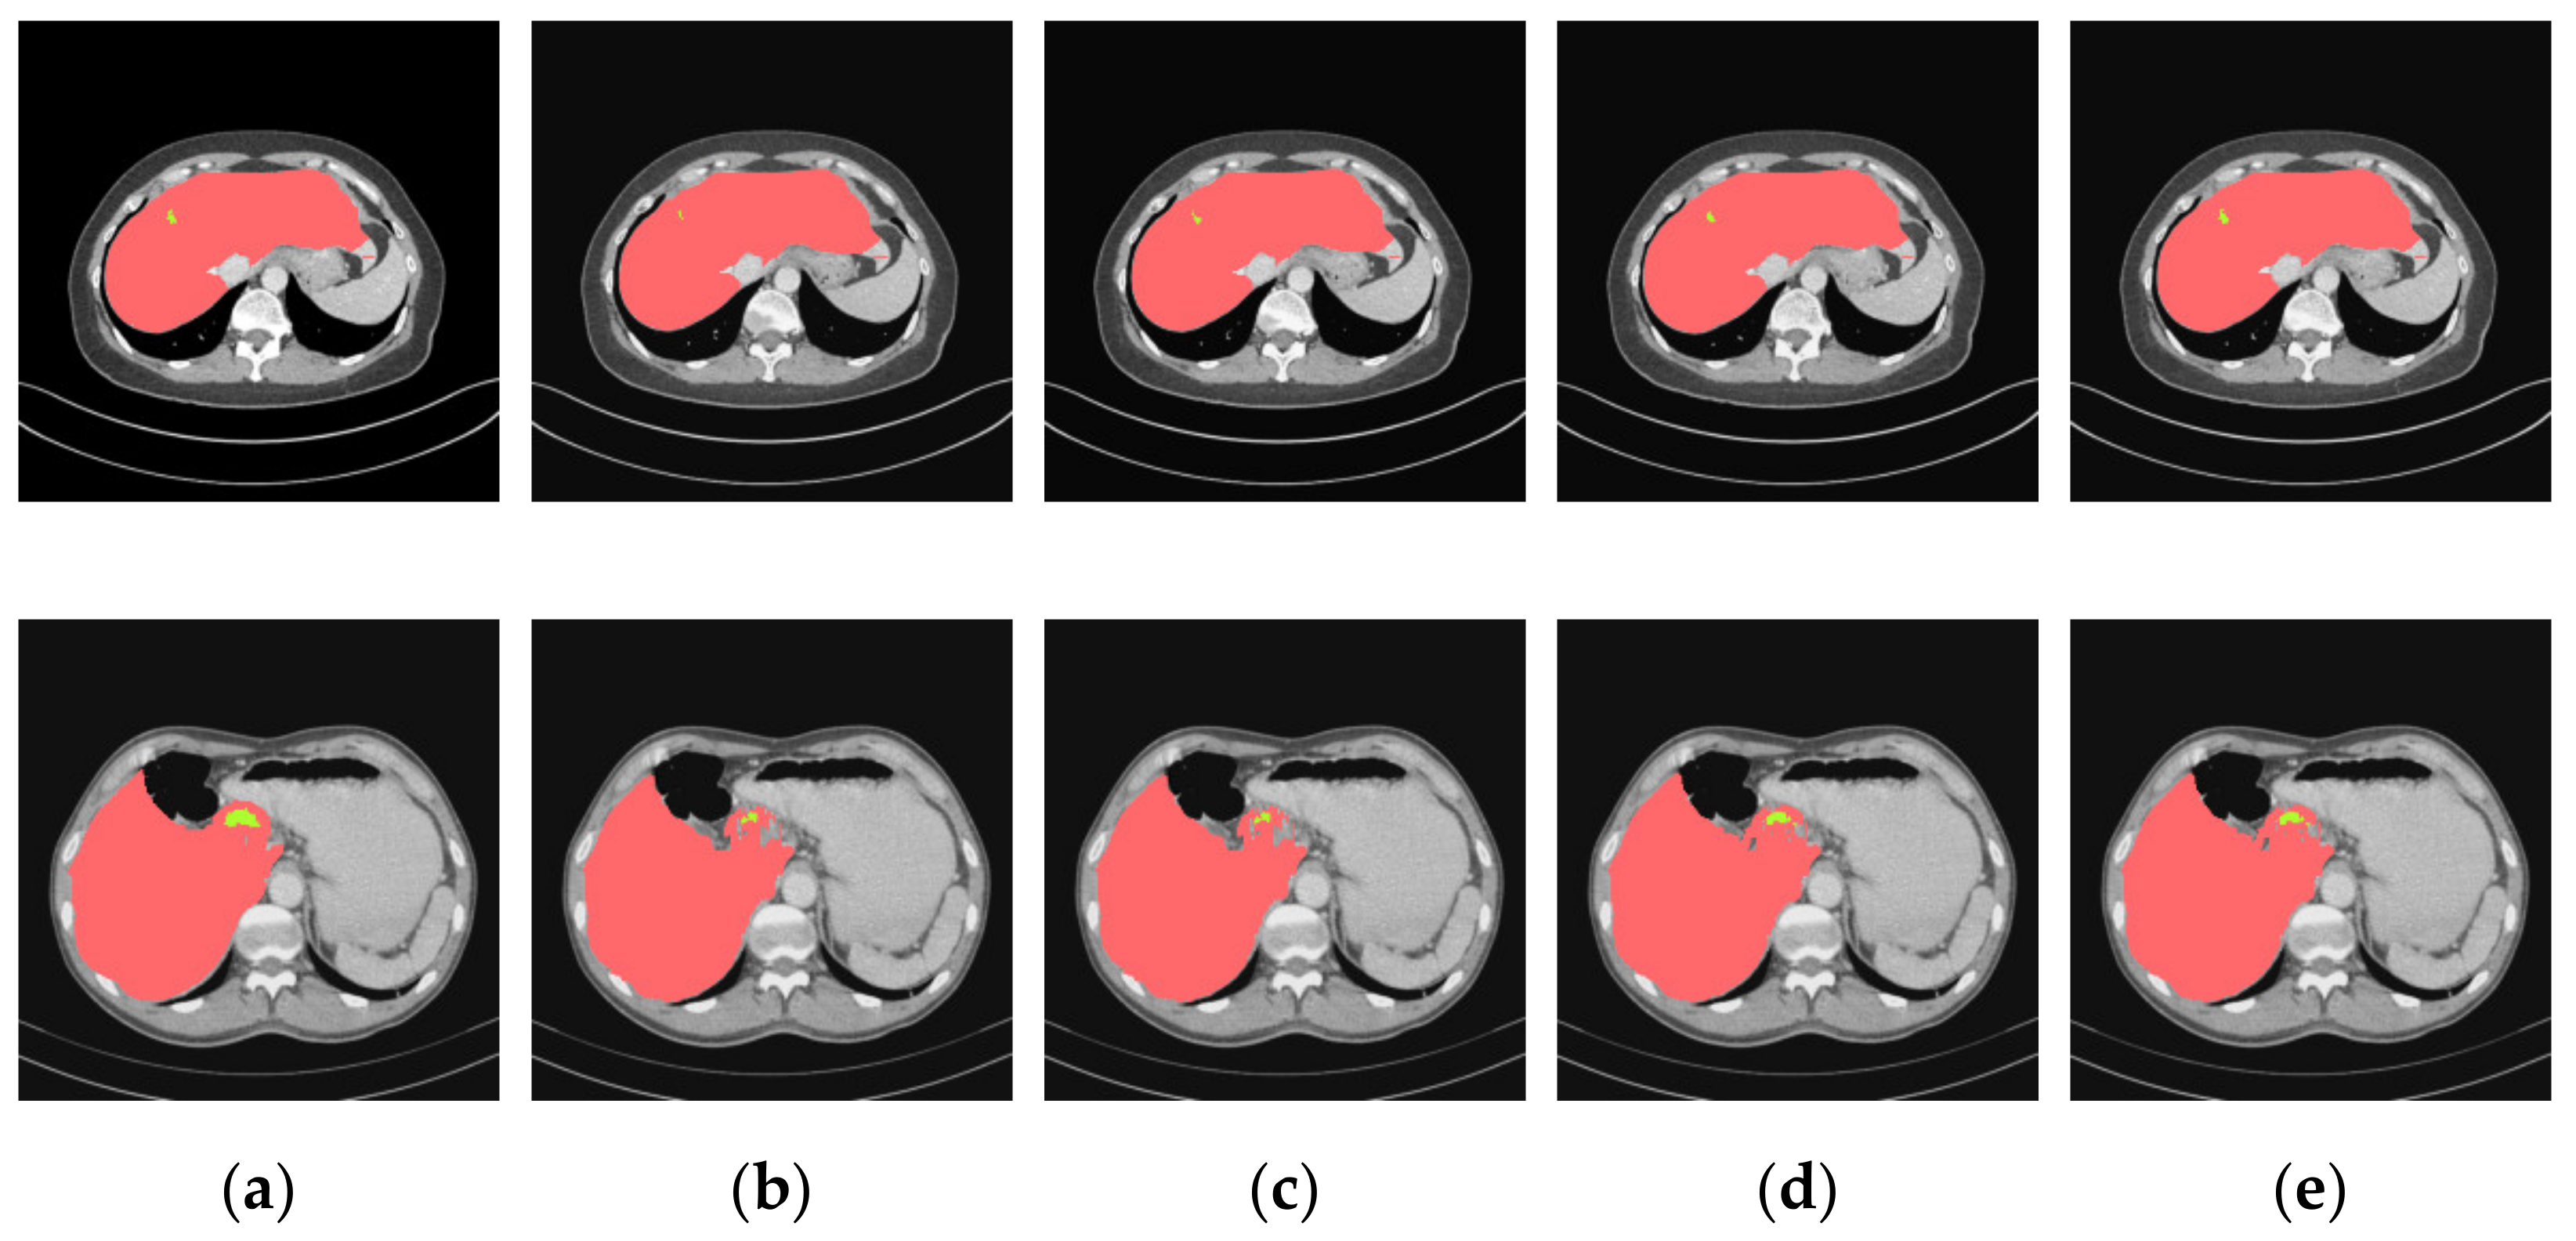

4.3.2. Analysis of Results in Three Patterns

4.3.3. Comparison of Various Algorithms